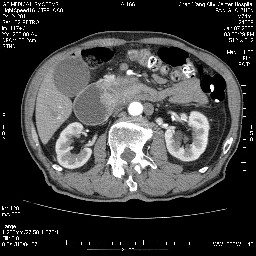

女,74岁,呕吐10余日

壶腹部的占位性病变,考虑为十二指肠癌并梗阻,但脾内多发性低密度区为转移吗?

还有胃、脾之间可见有侧支循环建立。左肾盂积水。

考虑来源于十二指肠水平段的恶性占位,侵及周围组织,特别是胰腺,可见区域淋巴结肿大,左侧下腔静脉畸形。

十二指肠水平段腔内占位伴梗阻,中等度较为均匀的强化,洗脱慢,区域淋巴结显示增多,符合腺癌表现。下腔静脉变异。

十二指肠降段扩张,水平段狭窄成鼠尾状,肠壁明显增厚,胰腺勾突增大成不均匀强化,其内可见低密度区,胆囊增大,1十二指肠水平段腺癌侵犯胰腺勾突可能大,2胰腺癌侵犯十二指肠(只有胆囊增大没有肝内外胆管扩张不好解释)代除外.

十二指肠降段扩张,水平段狭窄成鼠尾状,肠壁明显增厚,胰腺勾突增大成不均匀强化,其内可见低密度区,胆囊增大,1十二指肠水平段腺癌侵犯胰腺勾突可能大,2胰腺癌侵犯十二指肠 。

今日手术结果:胰腺钩突癌侵犯十二直肠,腹腔淋巴结转移.